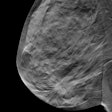

DBT surpasses FFDM in finding breast tumor margins